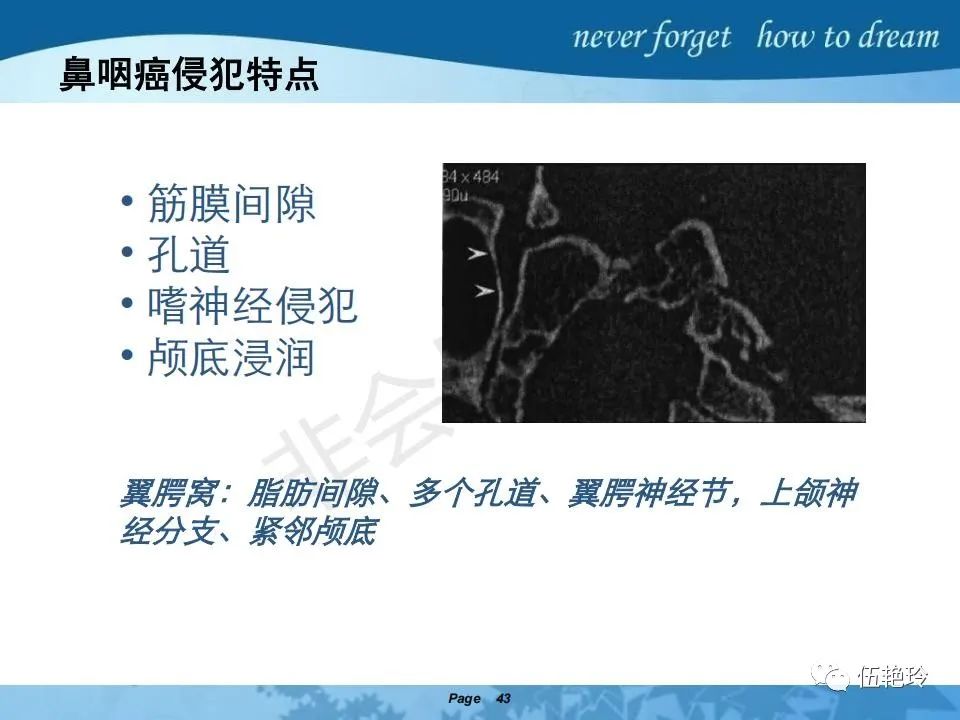

翼腭窝的解剖结构与鼻咽癌侵犯

2.2 鼻咽特有的解剖途径:鼻咽癌原发灶循序进展的总途径:鼻腔(47.8%)→翼腭窝(15.2%)→ 眶下裂(3.2%)→眶尖(1.2%)→海绵窦(0.6%)。

2.31 向上颅内:①鼻咽顶壁→破裂孔(岩尖、斜坡)→蝶窦、海绵窦;②鼻咽顶壁→蝶骨基底部→蝶窦、海绵窦;③鼻咽侧壁→茎突前间隙→蝶骨大翼(卵圆孔)→海绵窦;④鼻咽侧壁→茎突前间隙→翼腭窝→ 颞下窝;⑤鼻咽前壁→鼻腔→翼突、翼腭窝→眶下裂→眶尖→海绵窦;⑥鼻咽前壁→鼻腔→上颌窦、筛窦;